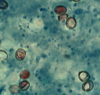

**Cryptosporidium**-oocysts in smear

58

**Cryptosporidium**-oocysts in smear

59

**Cryptosporidium**-oocysts in smear

60

**Cryptosporidium**-oocysts in smear